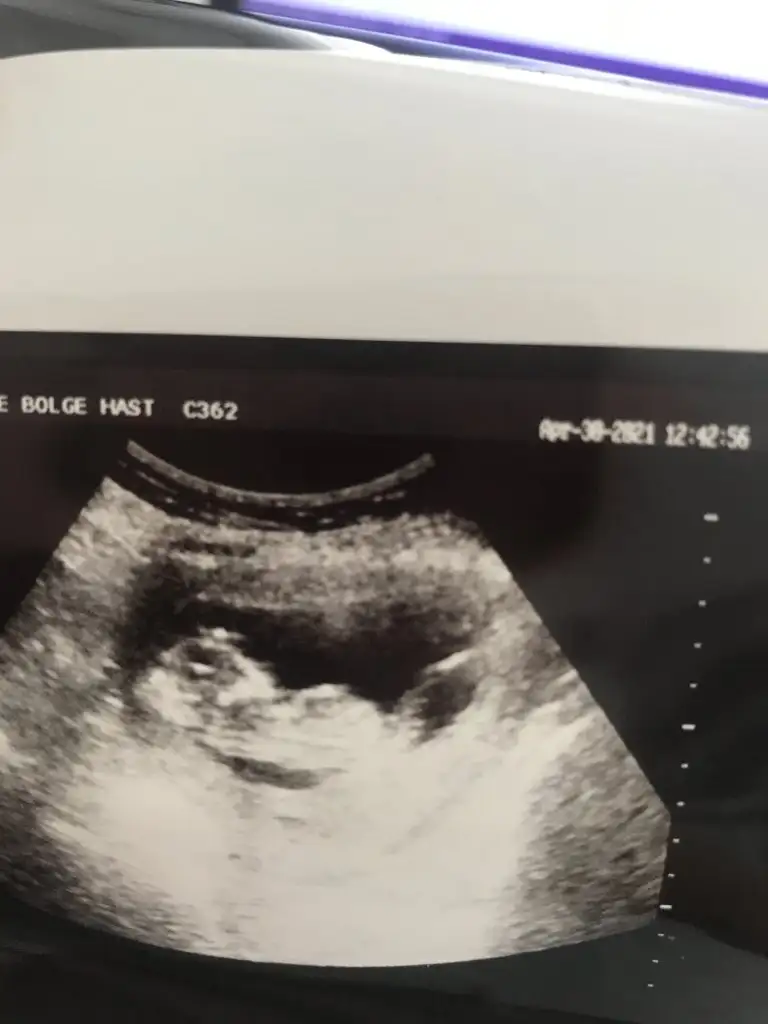

Merhaba lütfen tahmin yaparmısınız 2 yıl öncede yapmıştınız tutmuştu :)))

• 20210502_063913.webp

20210502_063913.webp

14,9 KB · Görüntüleme: 58

• 20210502_063853.webp

20210502_063853.webp

13,6 KB · Görüntüleme: 62